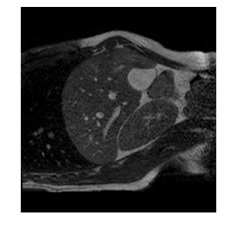

With this motivation, [6] proposed a convolutional neural network (CNN) based approach for temporal interpolation of navigators. Their CNN takes as inputs a fixed number of acquired images and learns to predict the missing images directly in the intensity space. This approach, which we call the Simple Convolutional Interpolation Network (SCIN), is a ’black-box’ formulation that does not incorporate any prior information about the interpolation process. Image prediction is guided only by the cost function used to optimize the network parameters. The issue with this is that it is unclear whether the image similarity measures that are generally used as cost functions suffice to ensure fidelity of the generated images to the original images. Indeed, Fig. 1b shows a case where an image interpolated using SCIN is quite blurry and misses several liver and lung structures present in the original image.

(a)                                (b)                                (c)

Figure 1: (a) Ground truth and (b,c) interpolated images from (b) baseline (SCIN) and (c) proposed method (MFIN). The image interpolated via SCIN is heavily blurred and misses several lung and liver structures, while the proposed method is able to preserve the details in the ground truth image.